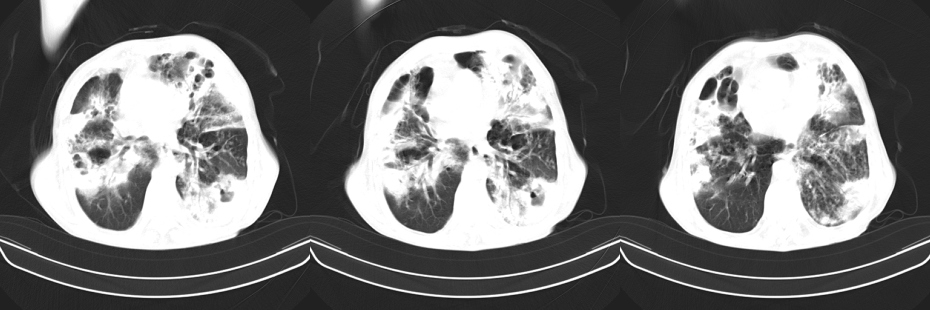

以下是引用mzh123在2007-8-26 19:58:00的发言:[br]两肺弥漫性斑片改变,其中可见大小不等之不规则空洞,结合既往病史还是考虑结核复发及感染。

以下是引用云翔在2007-8-26 20:54:00的发言:[br]这是44岁的肺吗?是否有先天病的基础?干酪性肺炎?